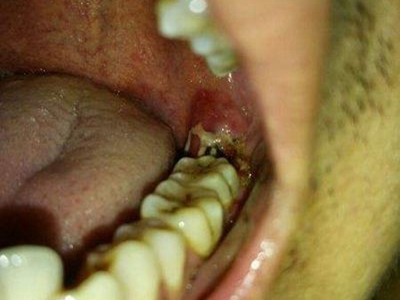

严重智齿冠周炎的图

严重智齿冠周炎患者智齿周围牙龈组织红肿、糜烂,还可见位置萌出异常的智齿,症状严重时炎症侵袭咀嚼肌,可导致不同程度的开口受限,有明显触痛,压迫时有脓血液溢出。